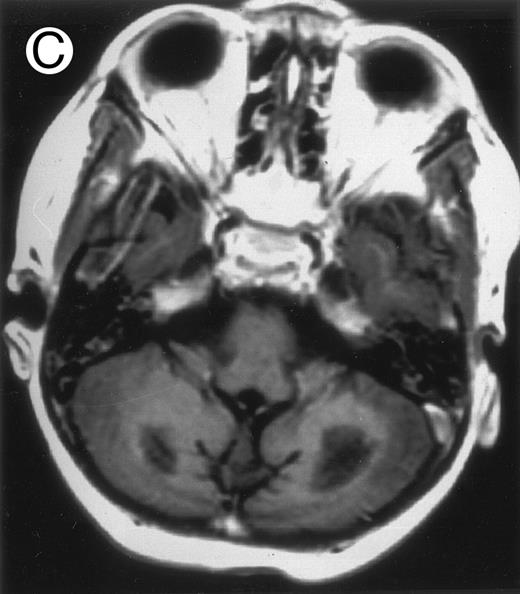

Three different aspects of brain imaging in HLH patients. (A) CT scan of a 3-month-old baby showing a large subdural effusion, several necrotic areas and hypodensities of the white matter. (B) Brain magnetic resonance of a 14-month-old boy showing large confluent areas of hypersignal in T2-weighted images. (C) Large symmetrical necrotic areas of cerebellar white matter in a 41/2-year-old girl (MRI).

Together, 19 patients had primary severe CNS disease progression or CNS relapse (Fig 1). Three of 19 had a CNS relapse characterized by meningitis only. Neurological symptoms occurred in 16 of these 19 patients (9 from the onset and 7 after the initial meningitis) (Fig 1). No clinical or neuroradiological difference was detected between the patients who developed neurological symptoms as the initial CNS manifestation or after initial meningitis (Table 1). The occurrence of these neurological manifestations marked a turning point in the evolution of the disease, as chemotherapy led to an improvement of the neurological symptoms in only three patients despite the use of intensive treatment by MTX IT. In these three patients, neurological sequelae persisted after the first symptoms and a relapse occurred within 3 to 10 months. Brain imaging was repeated during chemotherapy for four patients with progression of the CNS disease: in three patients, a severe brain atrophy developed (Fig 3A and B) and in the last patient who initially had contrast enhancement in cerebellar white matter, a cerebellum parenchymal loss was observed (Fig 2C). All of these 19 patients treated by chemotherapy only (n = 15) died during a last episode of coma and brain stem symptoms associated with a systemic hemophagocytic syndrome, 6 ± 6 months after the first neurological symptom (irrespective of the age at this first event). Four of these 19 patients were transplanted (one patient received an HLA-identical BMT, three an HLA-partially identical BMT). Median delay between diagnosis and BMT was 14 months (range, 2 to 20 months). All of these four patients died of BMT-related toxicity and/or disease progression.

Abnormalities on brain imaging appeared to roughly parallel the severity of clinical manifestations. All patients with neurological symptoms, but also half of the patients with initial meningitis, had abnormal brain imaging usually consisting of a combination of diffuse white matter abnormalities and necrotic areas with parenchymal volume loss, as previously described.8,23 In patients with isolated meningitis, however, only white matter abnormalities were detected, whereas necrotic lesions and cerebral atrophy were found in patients with neurological symptoms. These lesions progressed despite chemotherapy. Previous neuropathological studies have demonstrated infiltration by monocytes and activated lymphocytes of leptomeninges and brain parenchyma along penetrating vessels.24,25 Infiltration is associated with focal and confluent areas of myelin pallor, as well as neuronal loss, tissue necrosis, and cavitation,24,25 findings that were also demonstrated in the neuropathologic study of five patients in our series. Leukocytes infiltrating the CNS probably secrete cytokines and other neurotoxic factors, such as tumor necrosis factor-α (TNF-α), which may be responsible for the myelinic alteration observed in neurologically asymptomatic patients. Infiltrating leukocytes could also activate in parallel the numerous resident brain macrophages (the microglial cells) and astrocytes, which in turn, can secrete neurotoxic glutamate and free radicals.26